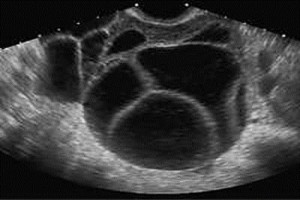

Diplomados en Ultrasonografía

Hola, conoce nuestros diplomados.